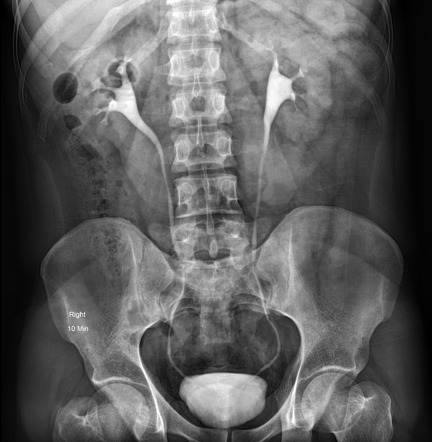

IVP

عکس رنگی کلیه یا IVP رادیولوژی از کلیه ها مجاری ادراری است. IVP به رادیولوژیست این اجازه را میدهدتا با مشاهده دقیق کلیه ها سرعت عملکرد سیستم ادراری بیمار را در دفع با هرگونه مشکل و اختلال را بررسی کند. این رادیولوژی بیشتر به منظور تشخیص علائم بیماری خون در ادرار، درد پهلو ، و یا سنگ در مسیر حالب به مثانه مورد استفاده قرار میگیرد.